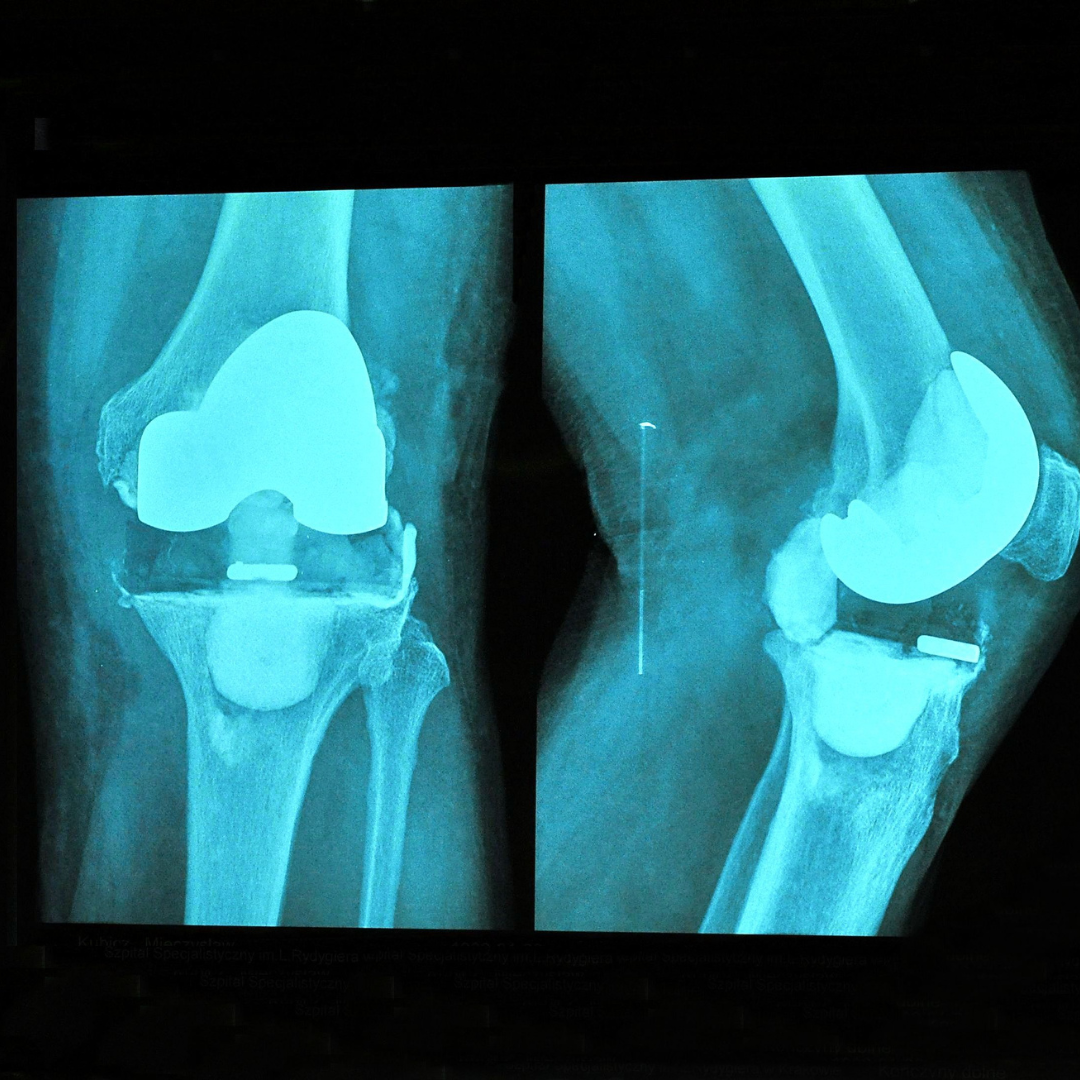

Running After a Knee Replacement

The research says it’s safe, but we’d like to see more. In a 2022 study, it looked at risk of revision after physically demanding activity post knee replacement. They looked at laborers and individuals who participated in “leisurely” activities that included high intensity exercise. The study DID NOT find any significant increased risk of revision with leisurely physical activity following the surgeries. The limitation of many studies like this, is that the quality of the reviewed studies were not great and so more research is needed to say this more confidently (1). With the current state of research on this topic, it may be safer to assume there is a potential risk you may shorten the lifespan of hardware by wear or loosening, but time will tell. These risks in my opinion can be mitigated with appropriate exposure to activity that improves bone quality and new growth to secure implants in cementless total knee replacements.

How long does a knee replacement last?

A study in 2019 looked at total knee replacements and unicondylar knee replacement (AKA partial knee replacement). They found that approximately 82% of total knees last 25 years and 70% of partial knees last approximately 25 years. This study did not further evaluate the activity level of the participants and thus we don’t yet know if type of activity reduces lifetime of the surgery before a revision is needed (2). With advancements in techniques and quality of materials, we think the hardware will last longer and longer in the future.